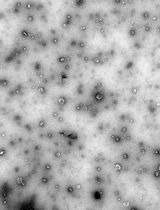

Interleukin-22 (IL-22) has been demonstrated as a critical regulator of epithelial homeostasis and repair; it showed an anti-inflammatory effect against ulcerative colitis. Local microinjection of IL-22 cDNA vector has been shown to be effective in treating ulcerative colitis in mouse models. However, microinjection comes with multiple technical challenges for routine colon-targeted drug delivery. In contrast, oral administration can get around these challenges and provide comparable efficacy. We showed in previous studies that oral administration of new lipid nanoparticles (nLNP)-encapsulated IL-22 mRNA targets the colon region and efficiently ameliorates colitis. This protocol describes the details of preparing and characterizing the nLNP-encapsulated IL-22 mRNA using three major lipids that mimic the natural ginger-derived nanoparticles. It provides an nLNP platform that can be used to orally deliver other types of nucleic acids to the colon.

We previously used ginger-derived lipid nanoparticles (GDNPs) for orally delivering CD98 siRNA (Zhang et al., 2017) and 6-shogaol (Yang et al., 2021) to treat ulcerative colitis. These studies suggested that GDNPs could overcome the challenges of oral drug delivery. Further, we found that monogalactosyl-diacylglycerol (MGDG), digalactosyl-diacylglycerol (DGDG), and phosphatidic acid (PA) constitute more than 90% of the total lipids of GDNPs (Zhang et al., 2016; Zhang et al., 2017). In this protocol, we will describe how to use these three lipids at the same ratios found in the GDNPs in the synthesis of new lipid nanoparticles (nLNPs) to encapsulate IL-22 mRNA. The nLNP-encapsulated mRNA showed its therapeutic efficacy in one of our recently published studies (Sung et al., 2022).